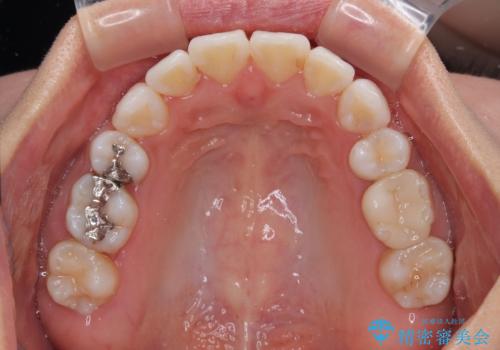

- 上下前歯の後戻りを気にして来院された患者様です。

インビザラインでの治療を希望されていて、デコボコの程度が中等度であり、安価なパッケージにて対応可能と判断されたため、インビザライン・モデレートを用いて矯正治療を行うこととしました。

インビザライン・モデレートは、製作できるアライナーの枚数に制限があるため、移動可能な量に限りがあるものの、インビザライン・ライトよりも枚数が多いため、幅広い症例に対応可能です。